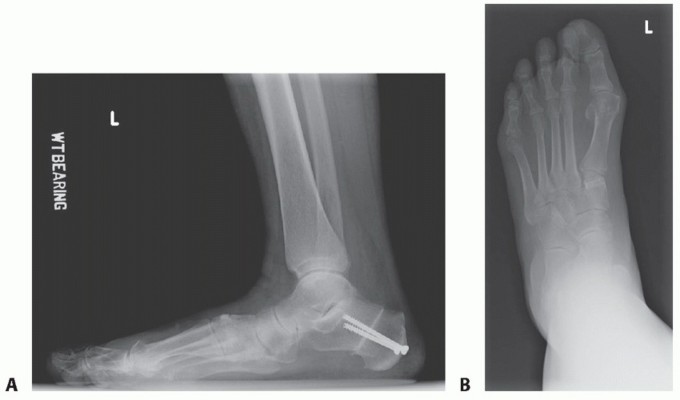

Clinical & Radiographic Imaging

Clinical Image